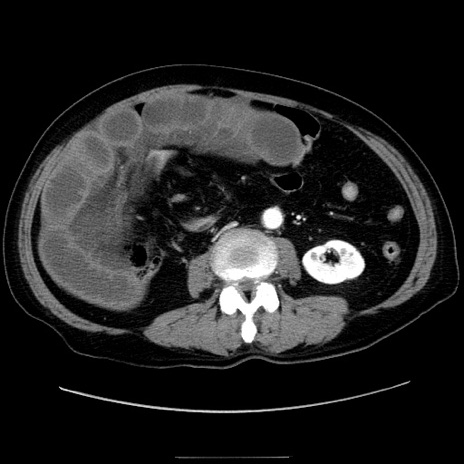

症例30(横断像)

【症例】80歳代男性

【主訴】臍周囲痛

【現病歴】約6時間前から臍下部痛が出現。次第に腹部膨隆・背部痛も生じてきたため来院。背部痛の場所は変化しない。

【身体所見】意識清明、BT 36.3℃、BP  131/87mmHg、P 87bpm、SpO2 100%(RA)、臍周囲自発痛・圧痛あり、反跳痛なし、自発痛部位に一致して板状硬あり、腹部膨隆、腸雑音減弱、CVA tenderness両側陰性。

【データ】WBC 19600、CRP 0.33